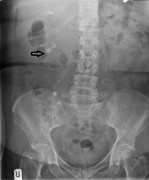

Chilaiditi's sign secondary to Richter's hernia or Chilaiditi's syndrome?

Vikal Chandra Shakya

Journal of Surgical Case Reports, Volume 2015, Issue 8, August 2015, rjv104, https://doi.org/10.1093/jscr/rjv104